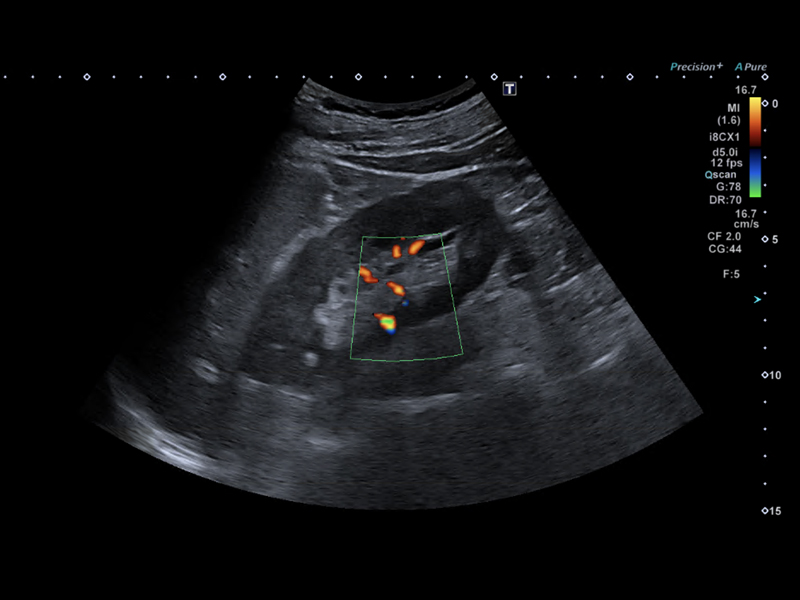

Ultrazvukové vyšetření radiologem

- pavilon B3 nebo B5

- lačnost

- žádanka vystavena elektronicky